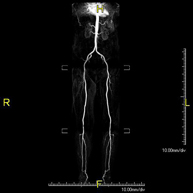

- Lower leg arterial MRI angiography

A non-invasive diagnostic screening that involves a vascular study of the aorto-iliac sector and the arterial vessels of both lower extremities, obtaining high-definition anatomical images using an electromagnetic field and radio waves (with transmitter and receiver). The use of paramagnetic contrast (gadolinium) is essential. However, it is a radiation-free procedure. The quality of the images allows for 2D and 3D reconstructions. It is particularly recommended for patients with suspected vascular disease in both extremities, patients with vascular disease in both extremities as a vascular map prior to treatment (percutaneous or surgical), as a pre-surgical vascular map in patients with bone or muscle injuries requiring surgery, etc.

A non-invasive diagnostic test that involves studying the abdominal aorta, obtaining high-definition anatomical images using an electromagnetic field and radio waves (with transmitter and receiver). The use of paramagnetic intravenous contrast (gadolinium) is essential. However, it is a radiation-free procedure. The quality of the images allows for 2D and 3D reconstructions. It is particularly recommended for patients with suspected vascular disease in both extremities, patients with vascular disease in both extremities as a vascular map prior to treatment (percutaneous or surgical), as a pre-surgical vascular map in patients with bone or muscle injuries requiring surgery, etc.